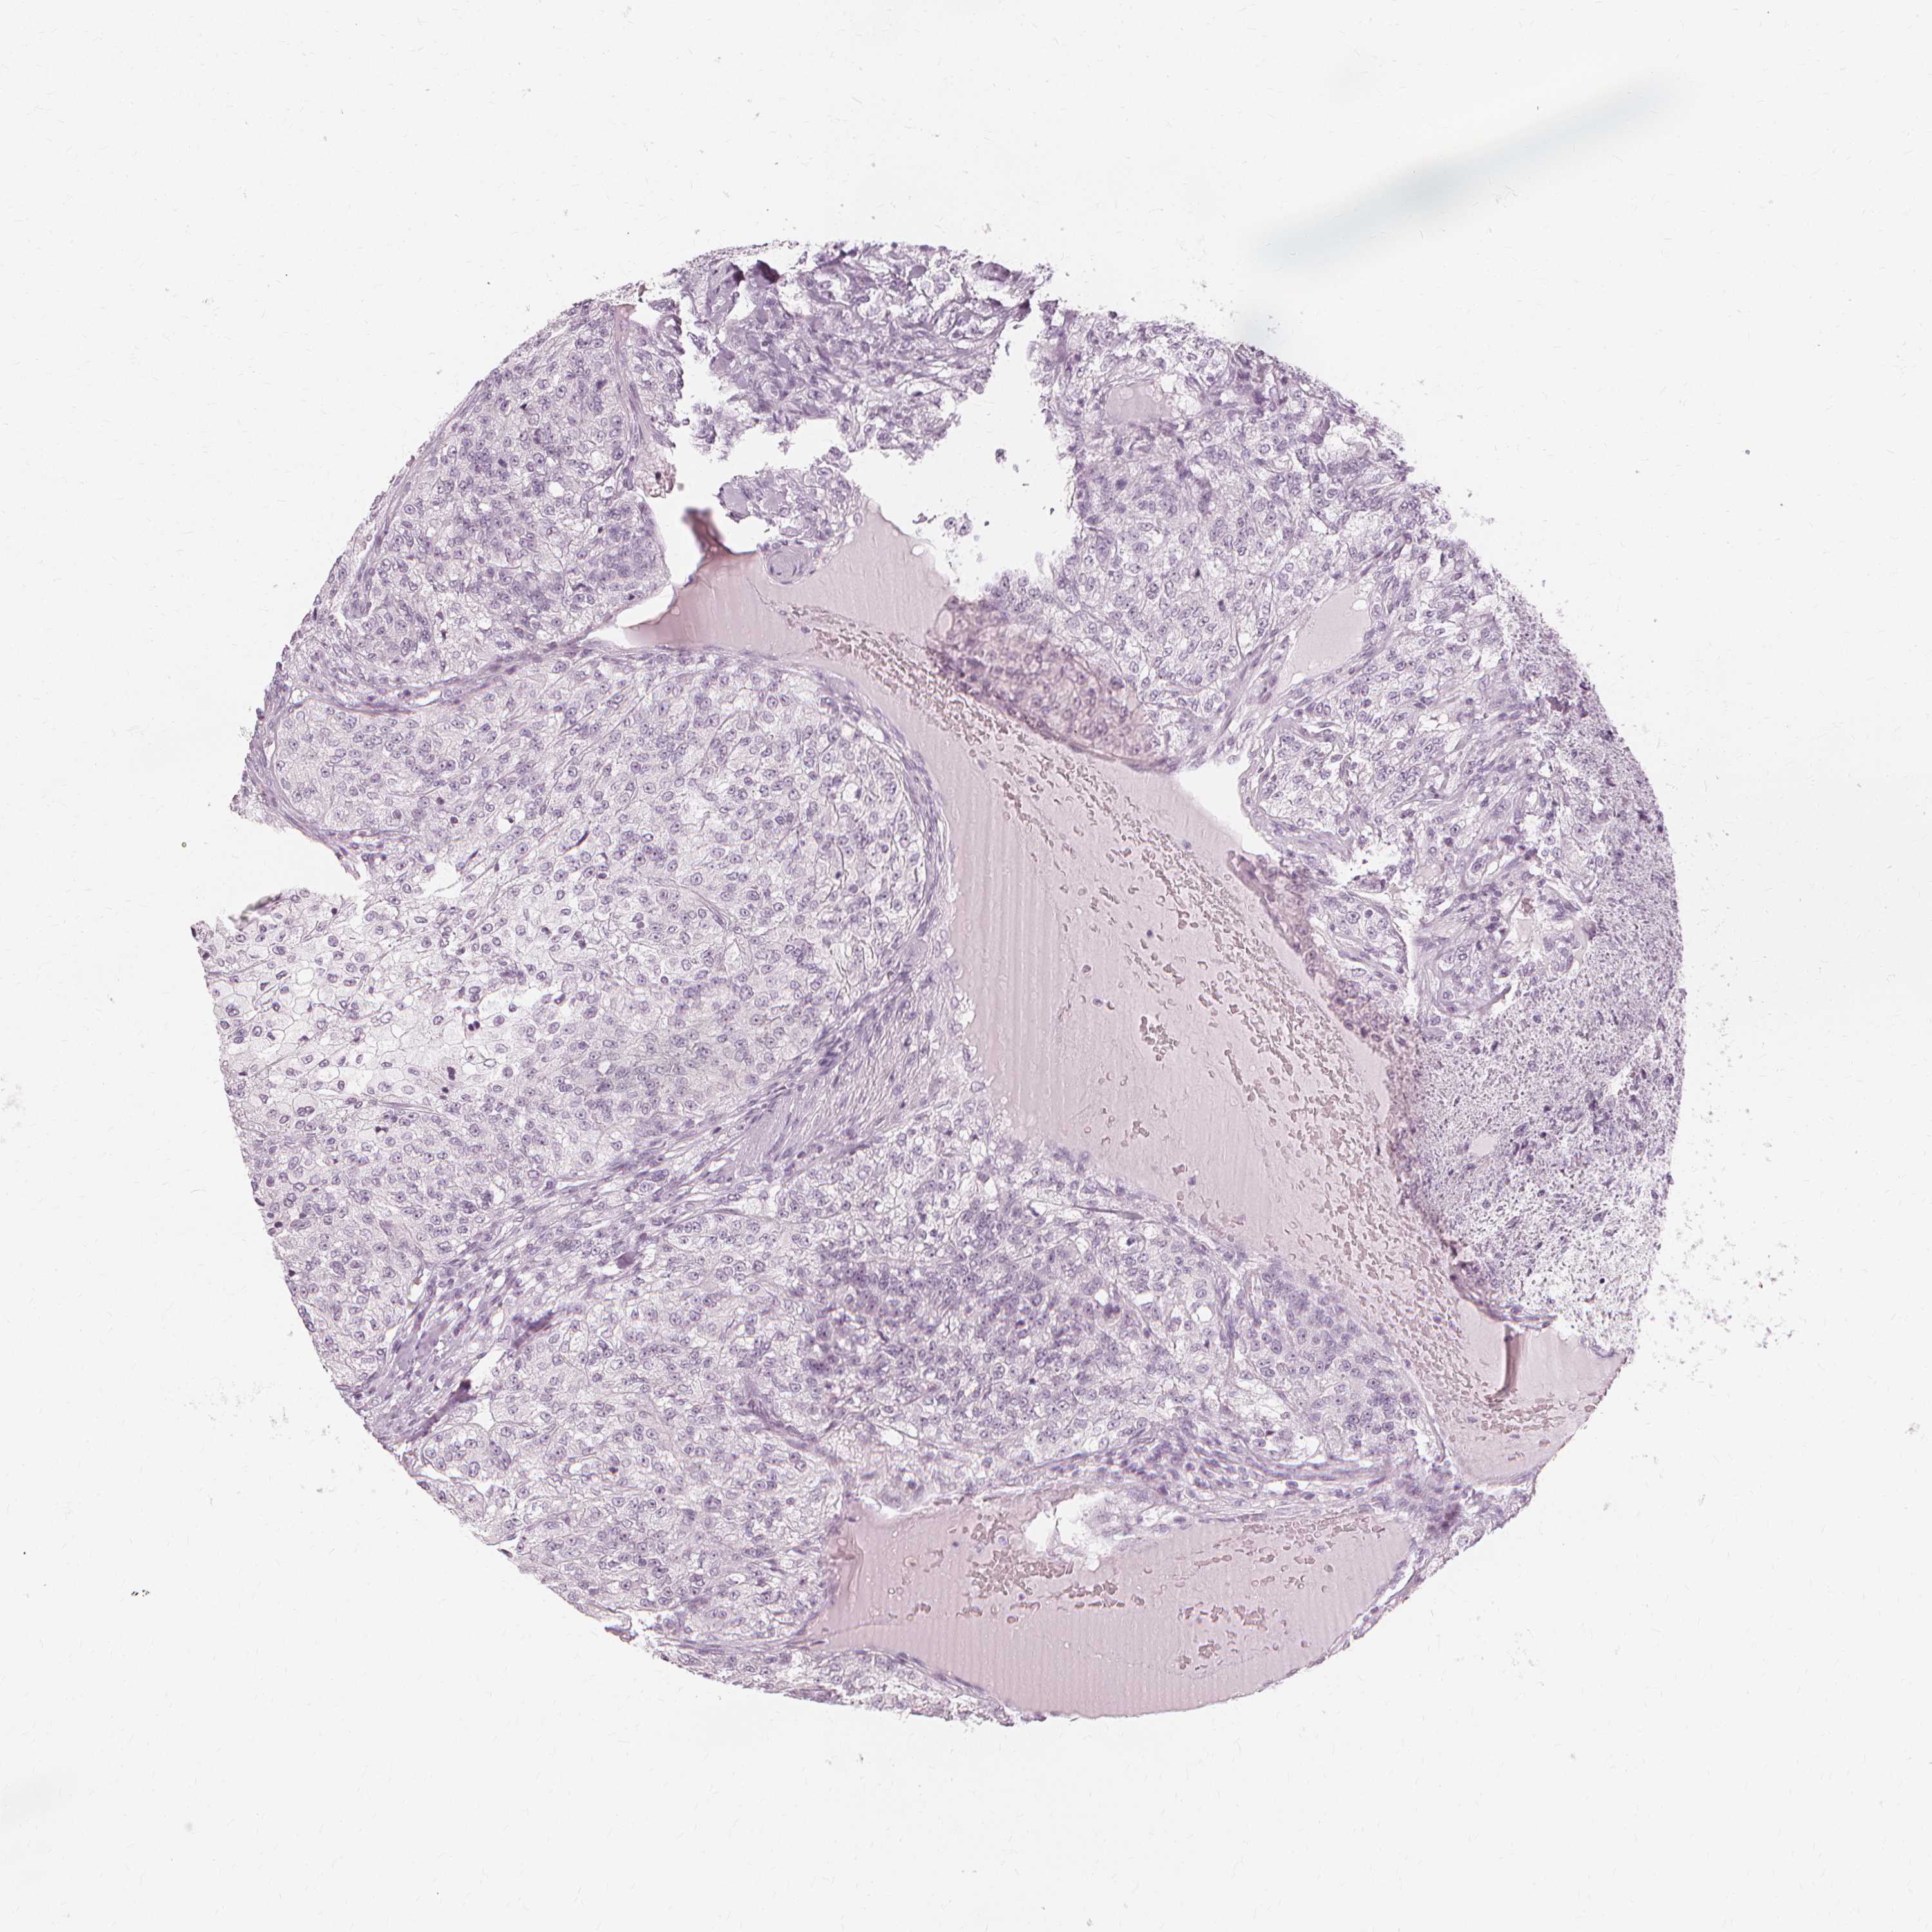

KIDNEY RENAL CLEAR CELL CARCINOMA (VALIDATION) - Interactive survival scatter ploti

The Survival Scatter plot shows the clinical status (i.e. dead or alive) for all individuals in the patient cohort, based on the same data that underlies the corresponding Kaplan-Meier plots. Patients that are alive at last time for follow-up are shown in blue and patients who have died during the study are shown in red.

The x-axis shows the expression levels (FPKM) of the investigated gene in the tumor tissue at the time of diagnosis. The y-axis shows the follow-up time after diagnosis (years). Both axes are complimented with kernel density curves demonstrating the data density over the axes. The top density plot shows the expression levels (FPKM) distribution among dead (red) and alive patients (blue). The right density plot shows the data density of the survived years of dead patients with high and low expression levels respectively, stratified using the cutoff indicated by the vertical dashed line through the Survival Scatter plot. This cutoff is automatically defined based on the FPKM cutoff that minimizes the p-score. The cutoff can be changed by dragging the vertical line or by entering a cutoff value in the square labeled "Current cut-off".

Under the Survival Scatter plot the p-score landscape (black curve; left axis) is shown together with dead median separation (red curve; right axis). Dead median separation is the difference in median mRNA expression between patients who have died with high and low expression, respectively. It is calculated as follows: median FPKM expression of dead patients with high expression - median FPKM expression of dead patients with low expression. This is intended to aid the user in visually exploring custom cutoffs and the associated p-scores and dead median separation.

Individual patient data is displayed and can be filtered by clicking on one or more of the category buttons on the top of the page. Categories describing expression level and patient information include: high, low, alive, dead, female, male and tumor stages. The scale of the x-axis can be toggled between linear and log-scale by clicking on the "x log" button. Mouse-over function shows TCGA ID, patient information and mRNA expression (FPKM) for each patient.

& Survival analysisi

Kaplan-Meier plots summarize results from analysis of correlation between mRNA expression level and patient survival. Patients were divided based on level of expression into one of the two groups "low" (under cut off) or "high" (over cut off). X-axis shows time for survival (years) and y-axis shows the probability of survival, where 1.0 corresponds to 100 percent.

NXPE1 is not prognostic in Kidney Renal Clear Cell Carcinoma (validation)

TCGA RNA samplesi

RNA-seq data is reported as average FPKM (number Fragments Per Kilobase of exon per Million reads), generated by the The Cancer Genome Atlas (TCGA) .

Normal distribution across the dataset is visualized with box plots, shown as median and 25th and 75th percentiles. Points are displayed as outliers if they are above or below 1.5 times the interquartile range. FPKM values of the individual samples are presented next to the box plot.

Average pTPM 0.0

Number of samples 100